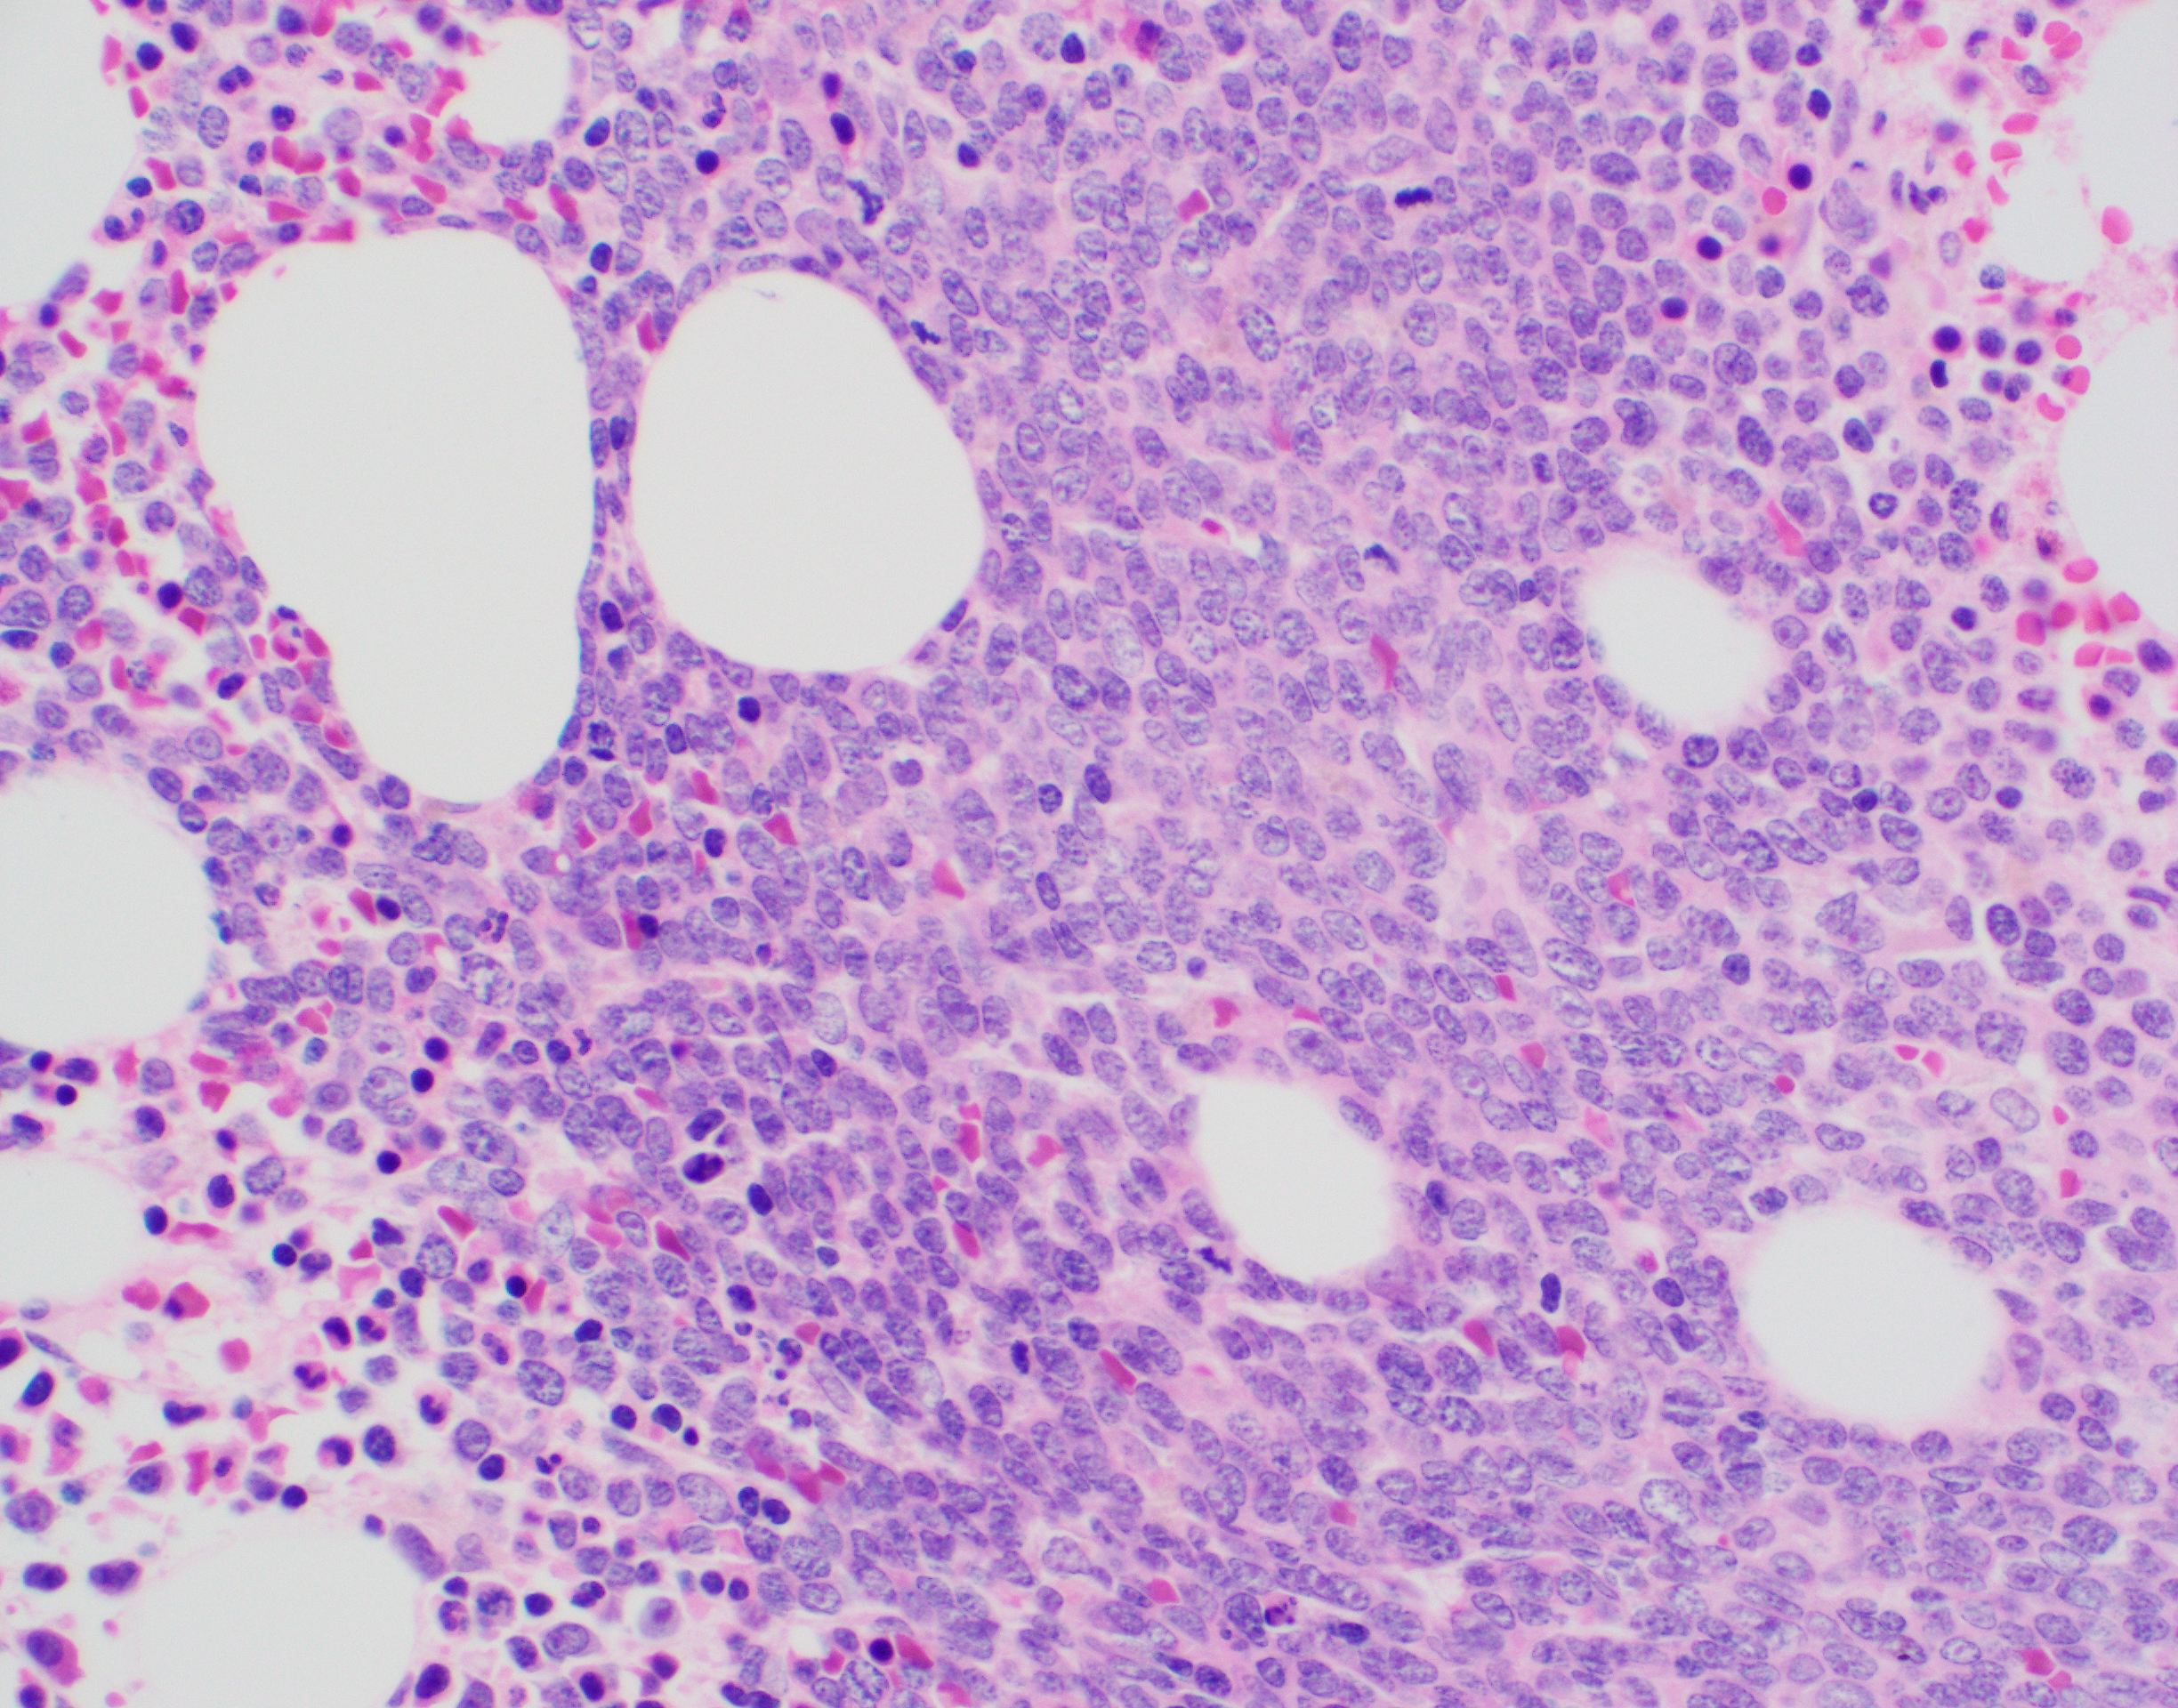

Review of the peripheral blood confirmed a markedly pancytopenic picture with virtually no leukocytes in the region of best RBC “spread” (Image 1A). In the periphery of the smear (1B and C) clusters of leukocytes were noted where left-shifted granulocytes were seen. Many demonstrated nuclear irregularity and abnormal granulation (B) and some showed the presence of numerous Auer rods (Image 1C, arrows).

The presence of abnormally granulated immature neutrophilic precursors, and cells with numerous Auer rods was morphologically compatible with acute promyelocytic leukemia (APL) and a rush preliminary diagnosis was rendered. The patient was started on ATRA therapy and FISH for PML-RARA was expedited.

Two distinct subtypes of APL exist: hypergranular (typical) or microgranular. The hypergranular variant is filled with large Auer rods and with dense cytoplasmic granules that can obstruct the nucleus. In contrast, the microgranular variant has a scantiness of cytoplasmic granules or small azurophilic granules.

The immunophenotype for APL is quite distinct and characterized by low or absent expression of CD34 and HLA-DR (in keeping with the cellular differentiation from blast to promyelocyte). APL cells are positive CD33 and CD13 with most cases showing expression of CD117 (sometimes weak). APL cells are usually negative for CD15, CD65, CD11a, CD11b, and CD18. The microgranular variant may display positive staining for CD34 and CD2. For both variants, IHC with antibodies to the PML gene demonstrates a nuclear multi granular pattern with nucleolar exclusion, a finding that is unique to APL and not seen in AML or normal promyelocyte morphology.